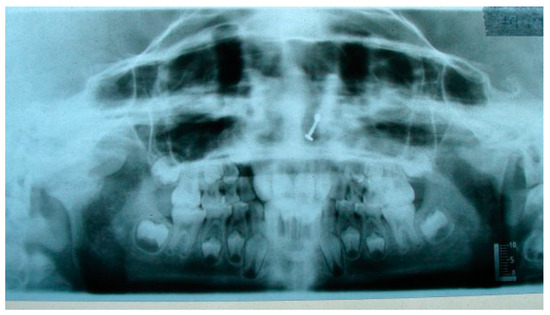

Figure 2. Postoperative OPG at 6 years of follow-up (black arrow depicting CCG graft with temporalis muscle interpositioning with respect to right temporomandibular joint).

The unique ability of the CCG to remodel into neocondyle could be well appreciated on the digital OPG and CT scan of the patient. The length and width of the neocondyle was very much comparable to the length of the condyle on the unaffected side at 6 years follow-up. Thus, the neocondyle formed using the costochondral cartilage was identical to the unaffected mandibular condyle both structurally and functionally. Poor socioeconomic conditions and lack of awareness coupled with poor primary health care facilities lead many of these unfortunate patients to live with this debilitating condition well into adulthood. Five such adult patients with age ranging from 17 to 36 years reported to us for treatment of TMJ ankylosis. In all these patients, ankylotic bony mass extends beyond the boundaries of the joint capsule. Alloplastic reconstruction after the release of ankylosis was our method of treatment, although high cost of condylar prosthesis led us to use 2.4 mm condylar head reconstruction plate along with temporalis muscle interpositioning in these patients. Interpositional grafts may fail to restore the ramal height in bilaterally ankylosed adult patients, so alloplastic condylar reconstruction may become the preferred choice. Advantages of alloplastic TMJ reconstruction are that the physical therapy can begin immediately, there is no need for a secondary donor site, surgery time is decreased, and alloplasts can be constructed in such a way as to mimic the normal anatomic contours of the structures they are to replace [17,18]. Wolford and Karras have suggested autologous fat transplantation as a useful adjunct to prosthetic TMJ reconstruction, as it minimizes the occurrence of excessive joint fibrosis, heterotopic calcification, and improves the range of motion [19]. However, they have categorically stated in their discussion that heterotopic bone formation is seen in multiple operated joints and joints with previously failed alloplastic implants. Another method to combat heterotopic bone formation is the use of 10 Gy of irradiation in five fractionated daily doses in the immediate postoperative period [20]. In our series, none of the patients reported with heterotopic bone formation possibly because they had undergone a single surgical procedure for managing TMJ ankylosis. The risk of fossa perforation could have been taken care by interpositioning of temporalis muscle in all these patients.